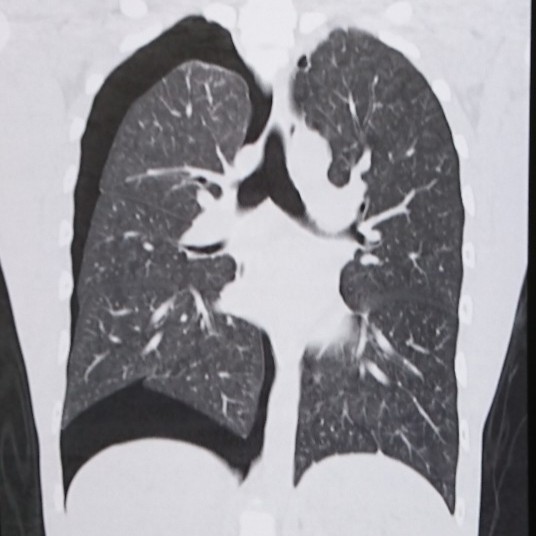

CTを撮れば一目瞭然です。

真っ黒のところは穴が空いてできた隙間です。

ほとんどの場合、穴が空くのは肺の上の方、鎖骨の近くです。